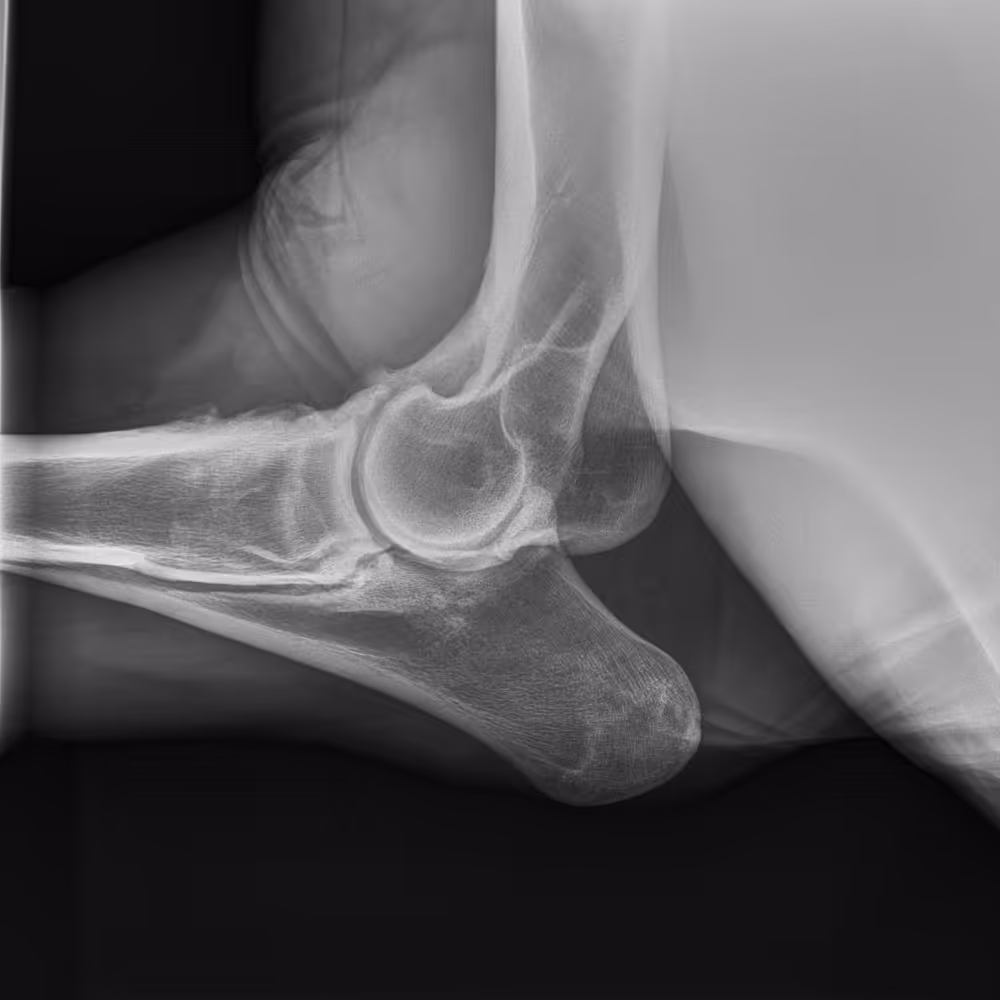

X-ray image

Severe OA of the distal intertarsal joint, progressing to ankylosis. Mixed subchondral bone loss and sclerosis are evident.

Severe OA of the distal intertarsal and tarsometatarsal joints, with significant joint space narrowing and subchondral bone changes (both sclerosis and loss).